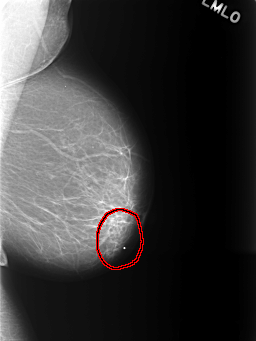

C_0401_1.LEFT_MLO

FILE: C_0401_1.LEFT_MLO.OVERLAY

TOTAL_ABNORMALITIES 1

ABNORMALITY 1

LESION_TYPE MASS SHAPE FOCAL_ASYMMETRIC_DENSITY MARGINS ILL_DEFINED

ASSESSMENT 3

SUBTLETY 5

PATHOLOGY BENIGN

TOTAL_OUTLINES 1

BOUNDARY